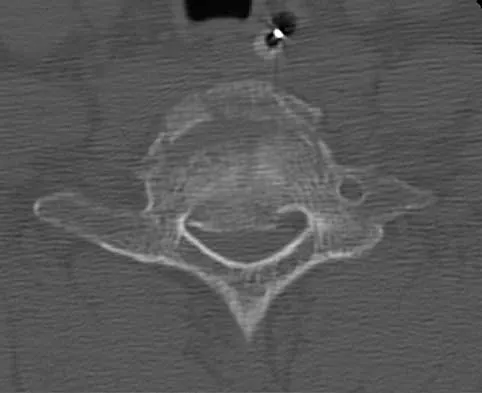

A paraplegic 32-year-old man was pulling himself up in bed by grasping the headboard rails when he felt a pop and immediate pain. A radiograph and CT scan are shown in Figures 2a and 2b. Based on these findings, management should consist of

The coracoid process is an essential component of the superior shoulder suspensory complex and must be maintained. Open reduction and internal fixation is recommended if the fragment is large and displaced more than 1 cm. Froimson AI: Fracture of the coracoid process of the scapula. J Bone Joint Surg Am 1978;60:710-711.